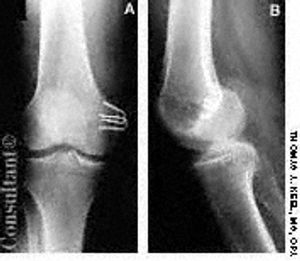

A 51-year-old man-a 6 ft, 240 lb bodybuilder-presented with long-standing, chronic rotational instability of the left knee as the result of a valgus blow to the joint during a football game 20 years earlier. The patient complained of extreme pain and reported that he felt the tibia sliding around under the left femur.